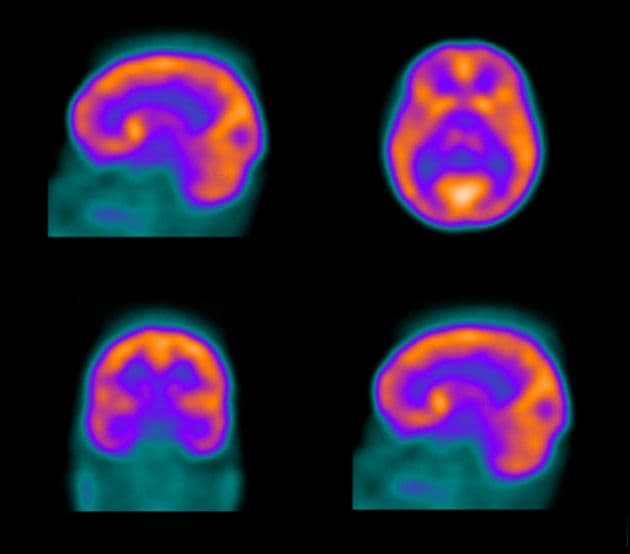

SPECT is a nuclear imaging test that is used to analyze the function of internal organs. Before the SPECT scan is performed patients are injected intravenously with a radioactive tracer substance. The tracer that is injected emits gamma rays and is able to cross the blood-brain-barrier. After receiving the tracer injection, patients typically wait for some period of time before the SPECT scan is performed in order to allow the tracer to reach the organ of interest. After this time has elapsed the patient will lay flat on a table. The SPECT scanner is a circular device that rotates around the patient. Attached to the device is a camera that detects the gamma rays emitted from the radioactive tracers. SPECT scans develop three dimensional images that can be used to analyze the function of internal organs. In the brain, SPECT is used to detect cerebral perfusion. Levels of cerebral perfusion may be an accurate representation of neurological condition as research has shown that cerebral blood flow is closely linked to neuronal activity.

SPECT may be used to detect functional damage from TBI that cannot be seen on other more traditional brain scans such as CT and MRI. When brain areas have been damaged as a result of TBI, SPECT scans normally show marked areas of decreased cerebral activity. In some cases cerebral hyperactivity has been observed over brain areas impacted by TBI. Research has shown that the severity of perfusion abnormality observed in SPECT scans may be correlated with the severity of TBI.